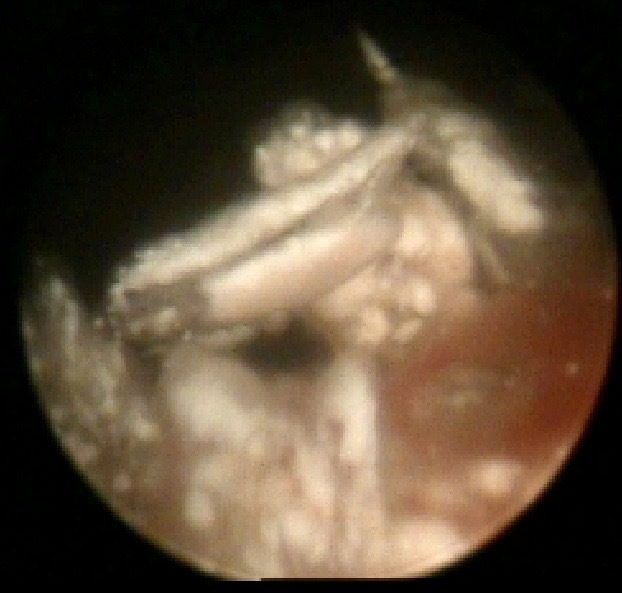

乍一看这张图,你是不是以为拍的是哪条地下河的钟乳石?其实,这是一位痛风患者膝关节镜下痛风石的模样!

男子告诉医生,他痛风10年了,最近就是因为两个膝关节疼痛难以忍受,弯曲不了,走不了路,实在没办法,近日才到医院求医。医生检查发现,在他本就狭小的关节腔内,“长”出了不少凹凸不平的锯齿状物,破坏了其关节面软骨。所以他的关节一活动,关节面相互摩擦,那种疼痛可想而知!

由于病情较重,经过医生的详细介绍后,林先生接受了膝关节针刀镜灌洗治疗术。在痛风石沉积的手指小关节、肢体浅表部位,医生则为他施以水筋针微创清理术。术后,林先生症状缓解,特别是原本难以弯曲、导致出现行走困难的膝关节终于可弯曲,活动自如。